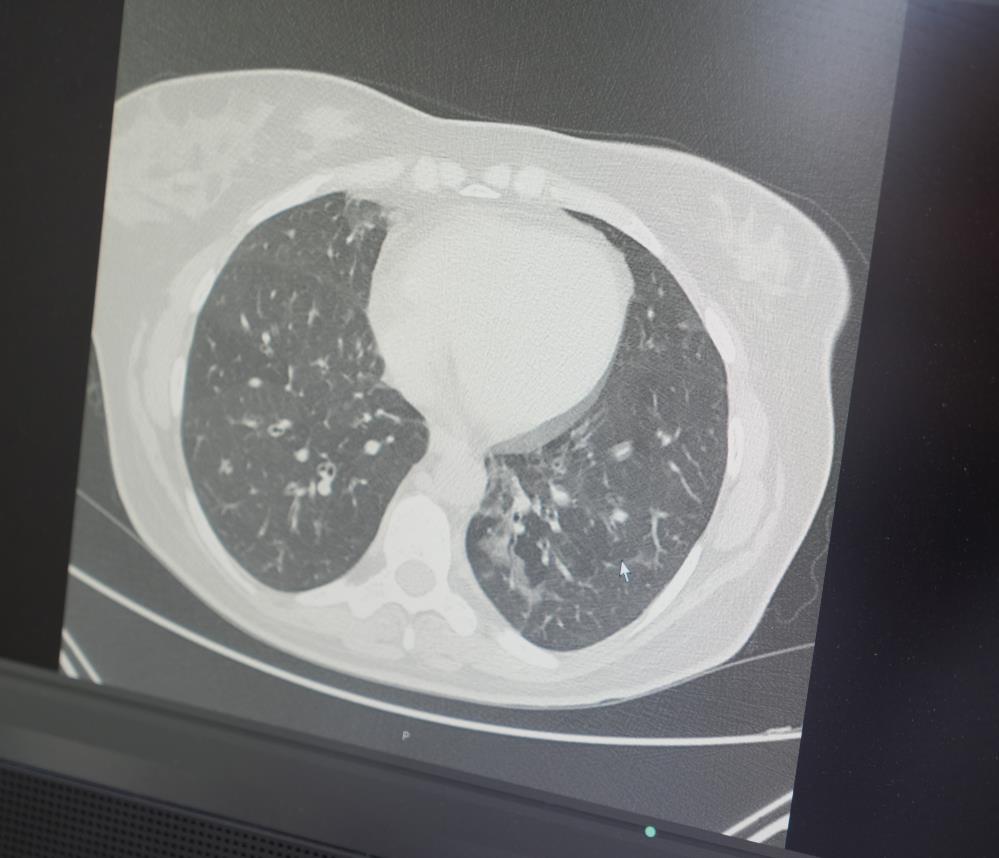

Covid-19'un yalnızca enfekte olduğu dönemde değil, uzun vadede de insan fizyolojisi üzerinde ciddi etkiler bıraktığını belirten Prof. Dr. Özkaya, “Pandemi, ilk teknolojik gelişmelerin ışığında izlediğimiz ölümcül bir salgın olarak tarihe geçti. Virüsün kılcal damarlarda bıraktığı hasar, neredeyse tüm hastalarda kalıcı etkiler oluşturdu. Özellikle 'sitokin fırtınası' adı verilen tablo, virüsün metabolik ve psikolojik farklılıklar yaratmasına neden oldu” dedi.

“Spor yapmaya devam eden bireyler arasında ani ölümler artıyor. Bu durum, akciğer ve kalp kılcal damarlarında Covid-19 kaynaklı kalıcı hasarlar ile ilişkili. Kış mevsiminin getirdiği soğuk hava ve ağır egzersiz birleştiğinde, kalp ve akciğer yeterli oksijen sağlayamıyor ve ani ölümler yaşanabiliyor.”